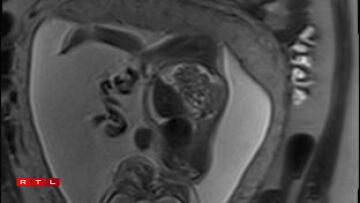

Lis was therefore referred to the Centre Hospitalier de Luxembourg (CHL), where further examinations led to a diagnosis. Noa was found to have a congenital pulmonary airway malformation (CPAM). Doctors explained that a large mass of cysts had formed in his chest, compressing his heart and disrupting his circulation. This, in turn, caused the fluid retention observed during the initial scan.

In Noa’s case, the CPAM was caused by a malformed aorta: a blood vessel had branched toward the lungs and was feeding the cysts. The condition is known as a sequestration. Professor Kohl proposed the following intervention:

“He would go through my abdomen with two small incisions to reach the amniotic sac, then pass through Noa’s chest to the heart, where he would cauterise the blood vessel that was feeding the cysts using a small electric current. From there, we could hope that the cysts would shrink and the lung could begin to develop”.